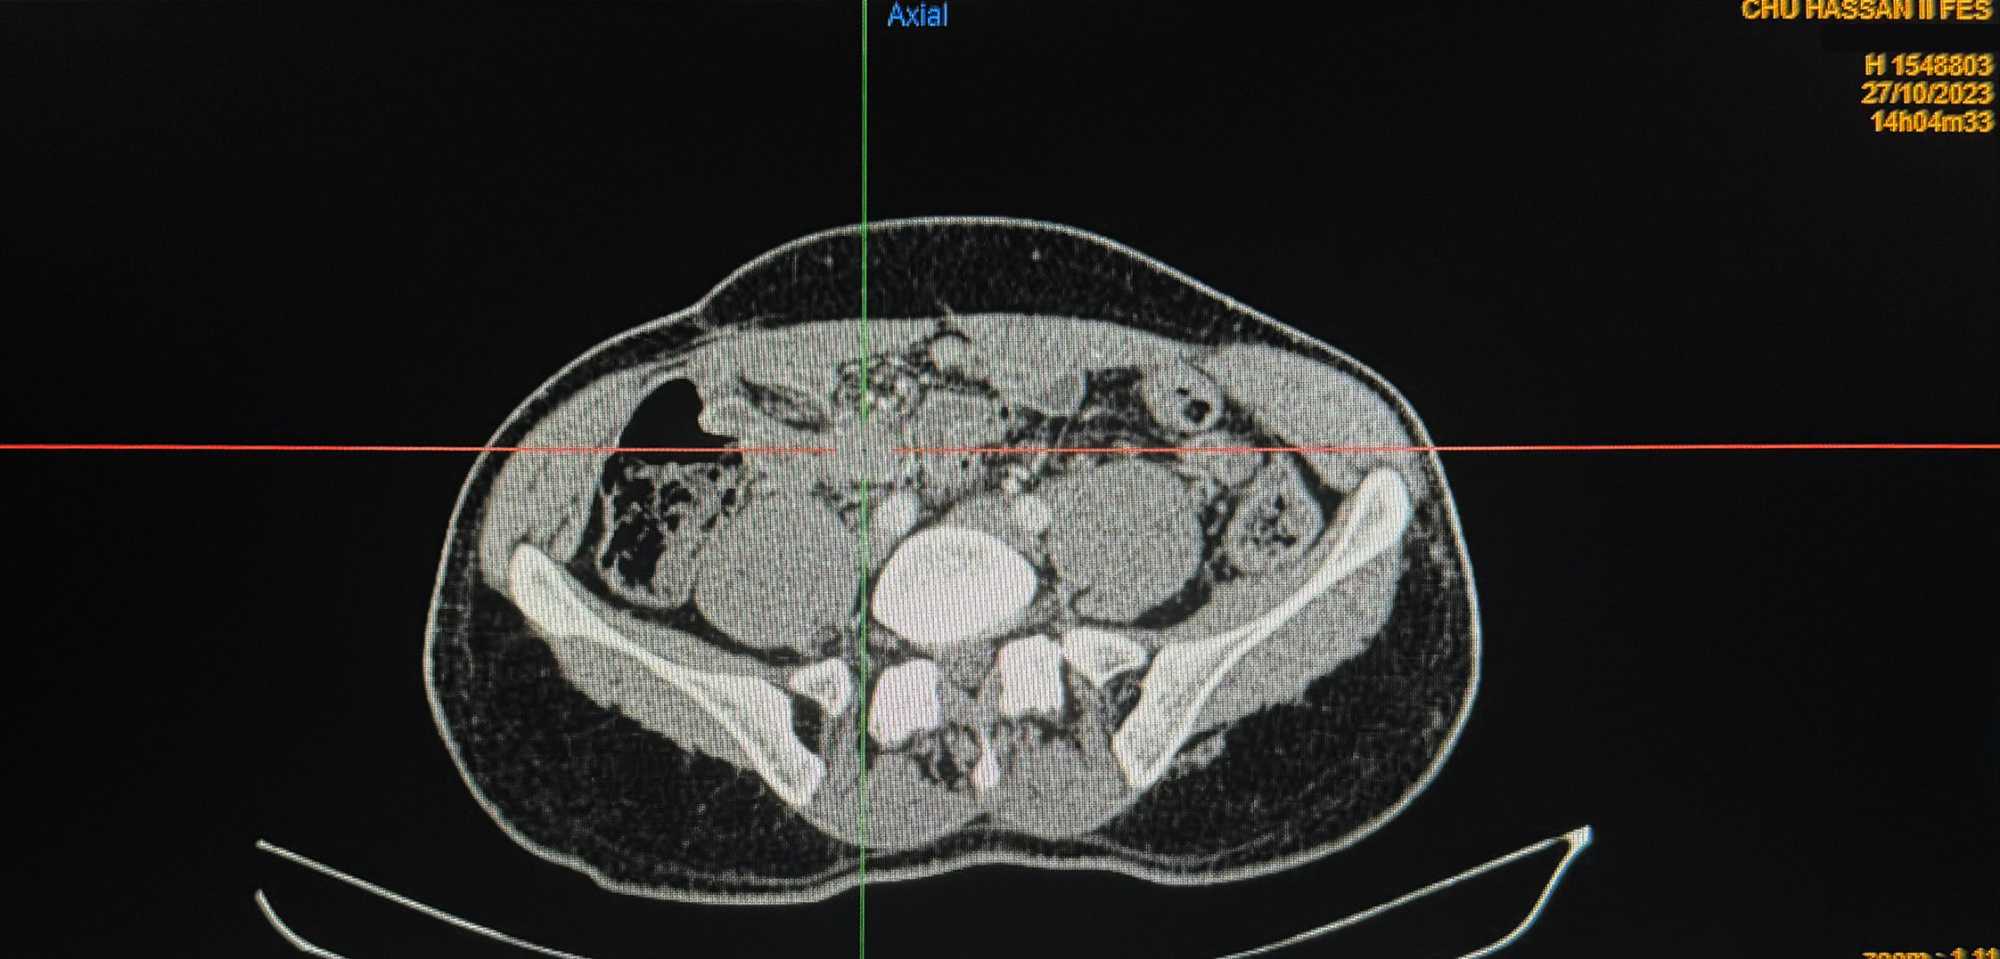

A reassessment CT scan performed on October 27, 2023 (Figures 1-4), after a year of treatment, showed partial regression of the tumor mass measuring then 30 × 18 × 34 mm.

Figure 2. Partial tumor regression on axial CT following 12-month sorafenib treatment.